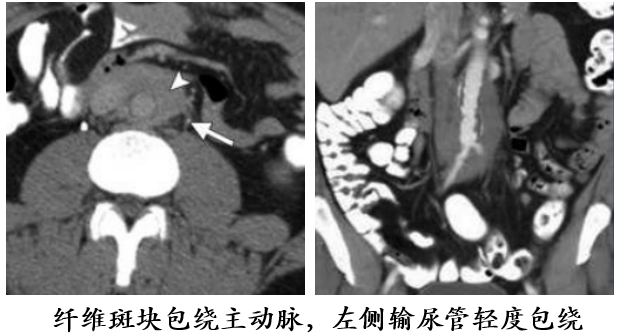

腹膜后纤维化

59 岁男性,增强 T1 显示腹主动脉前方软组织增厚,增强后病灶轻度强化。右侧肾盂及上段输尿管积水扩张,CT 增强显示双侧髂总动脉周围不规则软组织应包绕血管,右侧输尿管支架植入